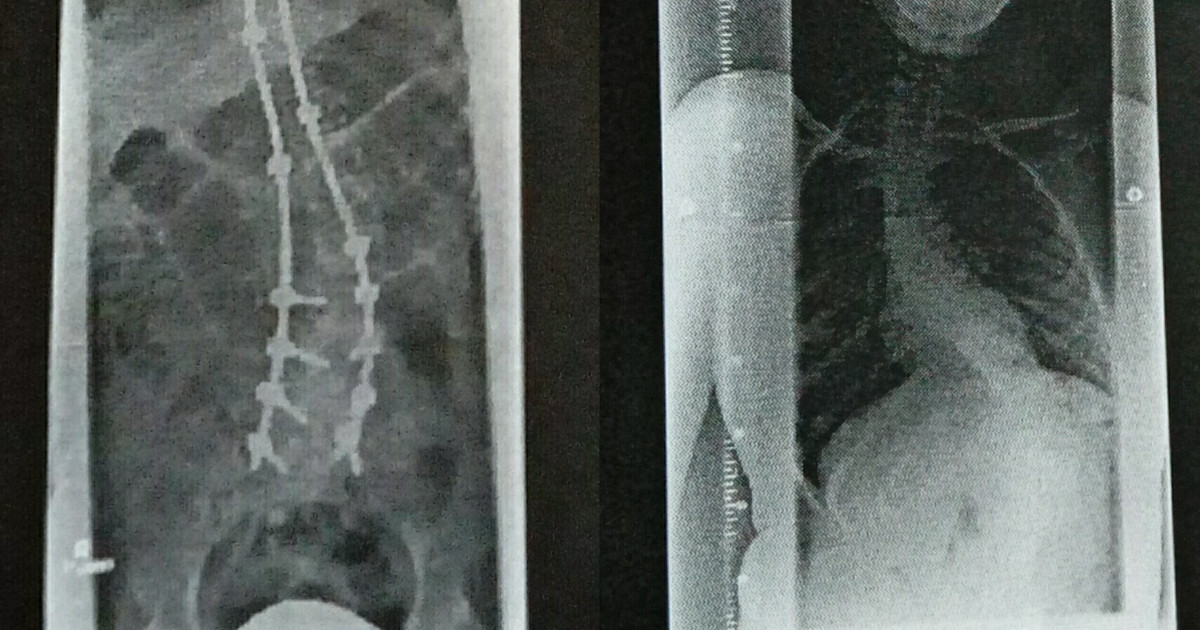

Bei der Operation wurde meine Wirbelsäule begradigt und von rechts und links wurden Titanstangen angebracht, damit die Wirbelsäule sich nicht mehr verkrümmen kann. Das alles wird Wirbelsäulenversteifung genannt. Ganz gerade bekamen die Ärzte meine Wirbelsäule nicht mehr, aus dem Grund haben meine Schultern heute noch eine unterschiedliche Höhe. Jetzt sitze ich immer sehr gerade, da ich die Wirbelsäule nicht mehr krümmen kann.

Am nächsten Morgen kam auf die Intensivstation eine Physiotherapeutin, die ich von der Routineuntersuchung kannte und ich sagte erstmal kräftig „Guten Morgen!“ zu ihr. Sie bekam fast einen Herzinfarkt, es war wohl nicht normal auf der Intensiv, aber wie gesagt, mir ging es gut. Schon am dritten Tag durfte ich wieder sitzen, es war etwas anders, da ich mich nicht mehr krümmen konnte und ich war auch ein paar Zentimeter größer, da die Wirbelsäule wieder gerade war. Auch der Buckel am Rücken war weg, ich sah schlanker aus, darüber freute ich mich. Dafür habe ich jetzt eine Narbe die sich über den ganzen Rücken erstreckt. Sie verheilte aber sehr gut und heute ist die Narbe kaum noch zu erkennen. Der Arzt hat bei der Operation wirklich sein allerbestes gegeben, deshalb vielen Dank an Dr. med. Dörner und sein Team! Mir wurde von den Ärzten gesagt, dass ich mich nicht mehr bücken kann, ich kann nur sagen, „Von wegen!“, es geht doch noch, man muss sich nur gerade nach vorne beugen. Von meinen Eltern habe ich die Einstellung mitbekommen „Geht nicht gibt es nicht“, deswegen probiere ich immer alles aus, wenn mir jemand sagt „Das geht nicht“, oder „Du kannst es nicht“.